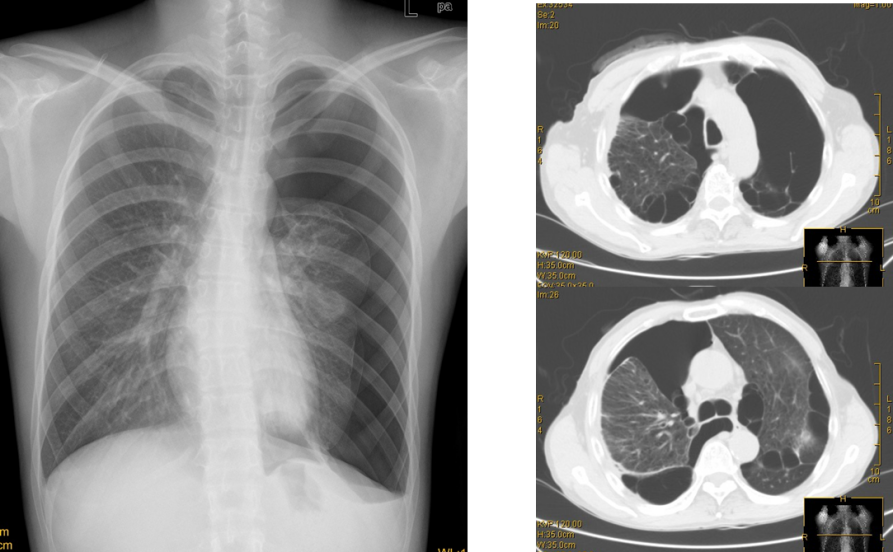

(5)气胸:继续使用导课的病例,说明气胸后出现病情变化,结合X线改变,讨论其体征产生机制,再次把以病人为中心的理念告知学生,把思政融入课堂。准备一张单纯气胸X线改变,一张COPD合并气胸CT改变(导课病人),与学生讨论其不同的体征及产生原因。(8min)